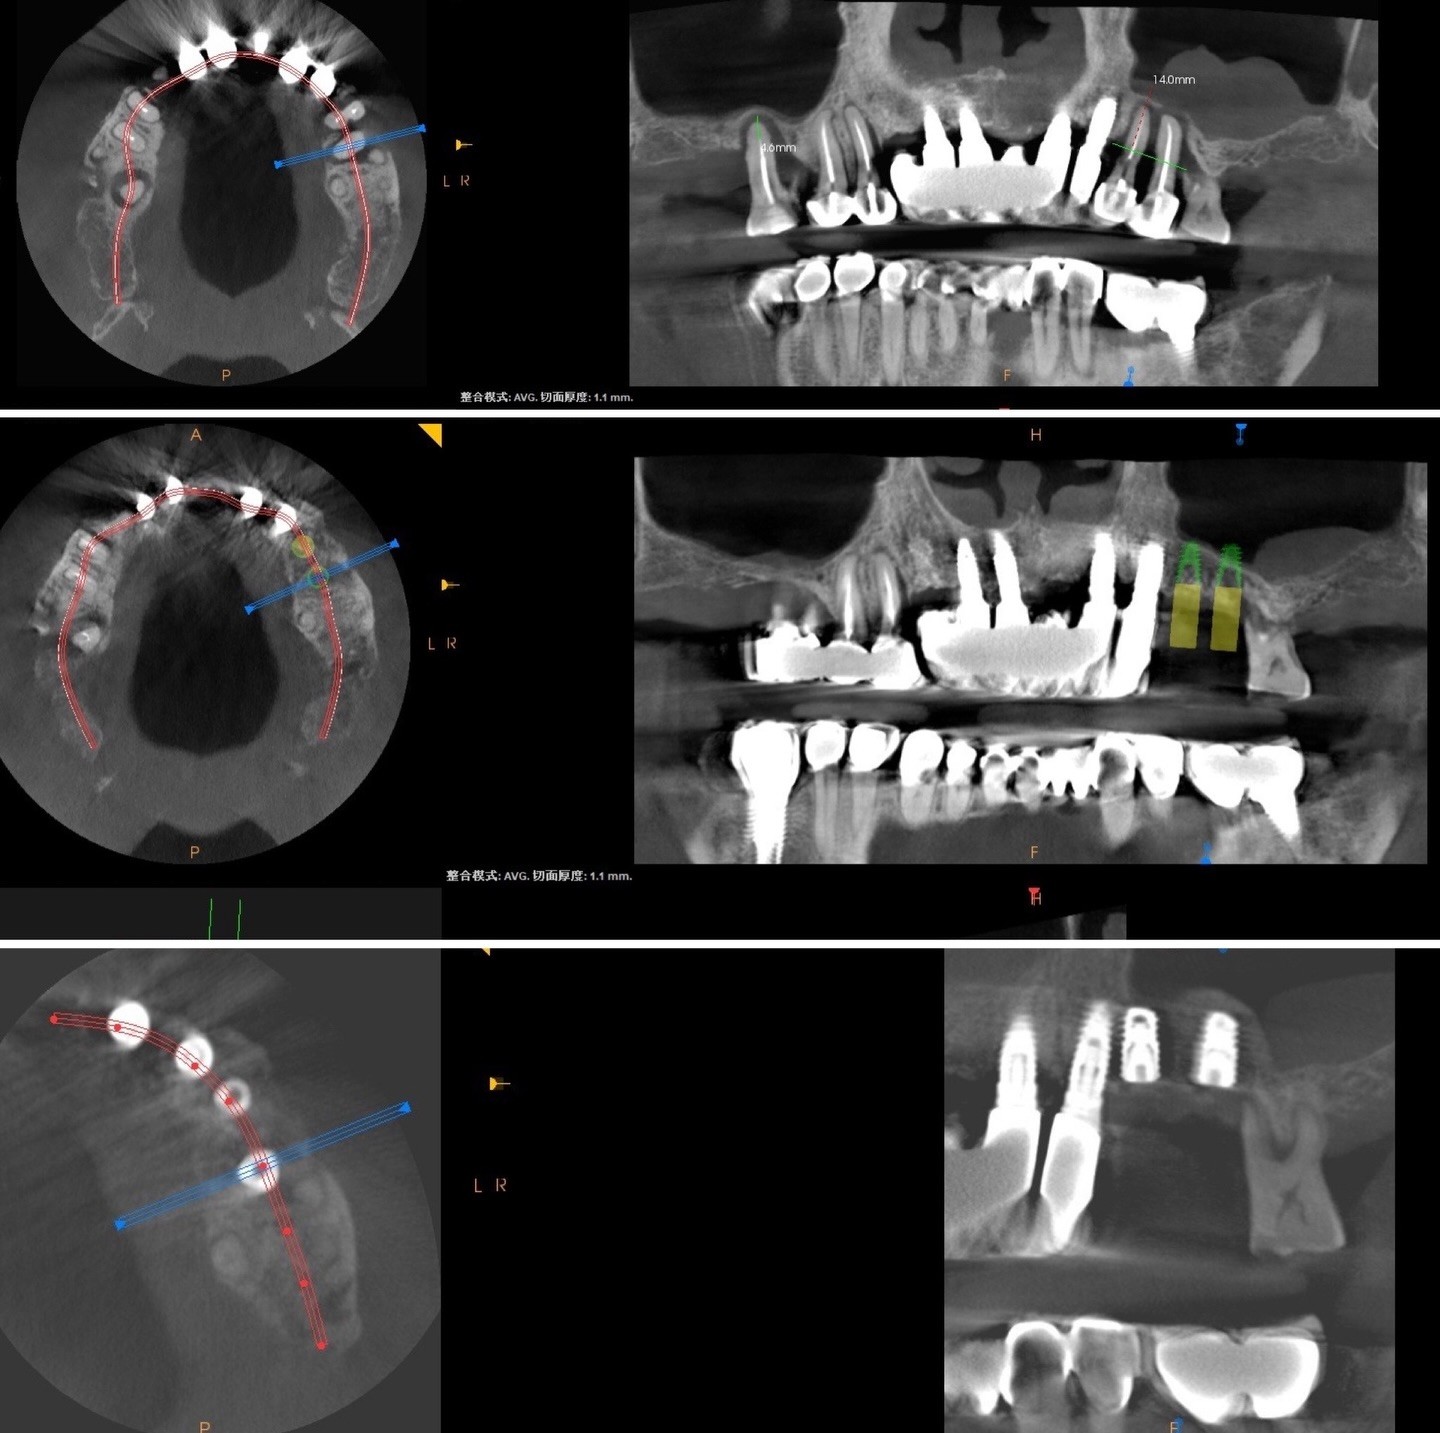

來的時候我們發現牙周狀況真的不是很好,上顎的左上其中兩顆牙,周圍基底幾乎掏空;沒有了骨頭!可想而知,牙齒君們是搖搖欲墜的狀態。

在術後的9個月,執行了植牙手術,由於患者本身的自我條件較不足,在手術的同時,還是一起進行了鼻竇增高術:

這也是補骨的一種,解決上顎植牙時因骨頭不足的問題,往上推高鼻竇底部的黏膜,在撐出的空間填入骨粉,以增加骨頭高度和密度,來確保植體有足夠點去支撐,藉此提升植牙成功率,以避免植體穿破鼻竇膜造成鼻竇炎。

2022年的年底,Y小姐經由姐姐的介紹,來找簡院長諮詢左下缺牙區的重建;君悅團隊跟Y小姐討論後,我們在23年的一月決定選擇較完整且成功率較高的植牙模式重建,於是先製作維持器以維持著上牙的位置(不讓上牙往下長,現在維持器可以當作咬合板暫用),然後做小臼齒的拔牙補骨,再把後方不密合的假牙製換掉,接著將大臼齒的骨頭補寬,於大24年六月植入兩根人工植體,八月補牙肉(同一位手術建議隔兩個月,讓血管長好),最後在24年十一月完成假牙(預計這個月迎來第一次門診追蹤)。之所以說較完整且成功率較高是補了骨頭和牙肉,且一次只做一件事情(補骨與植牙分開做),這樣可以提供植體周遭較多的骨頭和硬的牙肉(在想同得照護下,未來的使用年限會較長),但缺點是費時、費用較高,手術次數較多;所以若一開始的討論為快速成果較一般的植牙方式,院長會採取拔掉小臼齒同時即植入兩顆植體,並且在半年內開始製作假牙,將治療時間從將近兩年變成數個月,手術次數變成一次,費用會減少1/3左右。所以經由醫師的評估和明,君悅團隊給予醫病討論完最合適的治療計劃一直是院長致力於君悅要達到目標。

齒槽骨保存術是君悅一直有在做的手術,本篇文章是整理出六月簡院長做的三台手術的X光片,可以看出牙齒拔掉後放入骨粉的樣態,數個月後(通常等半年),這些骨粉會漸漸被自己骨頭取代,在片子上就不會看出骨粉與拔牙窩壁壘分明的樣子。院長想提醒醫師們,須留意舌側皮瓣,因舌側骨頭通常較多,在撥鬆皮瓣有時會造成皮瓣的破裂,建議慢撥控制力量並貼著骨壁走。院長也認為即拔即種對患者有省時少手術的優勢,若條件許可應該要跟患者建議。